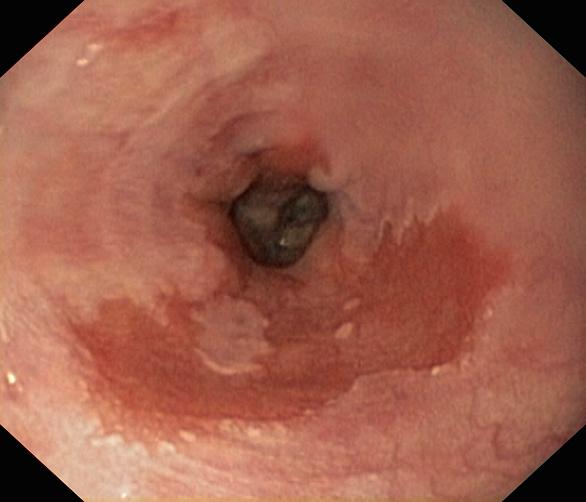

Przełyk Barretta